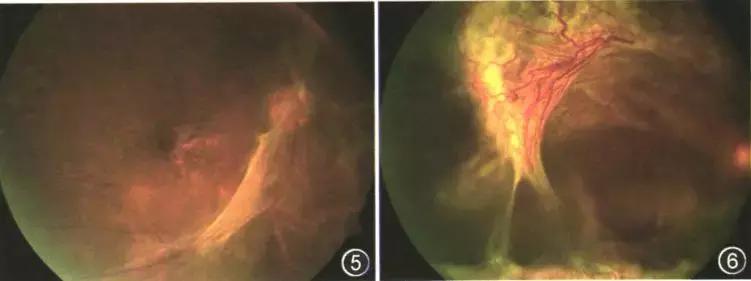

糖尿病视网膜病变分期